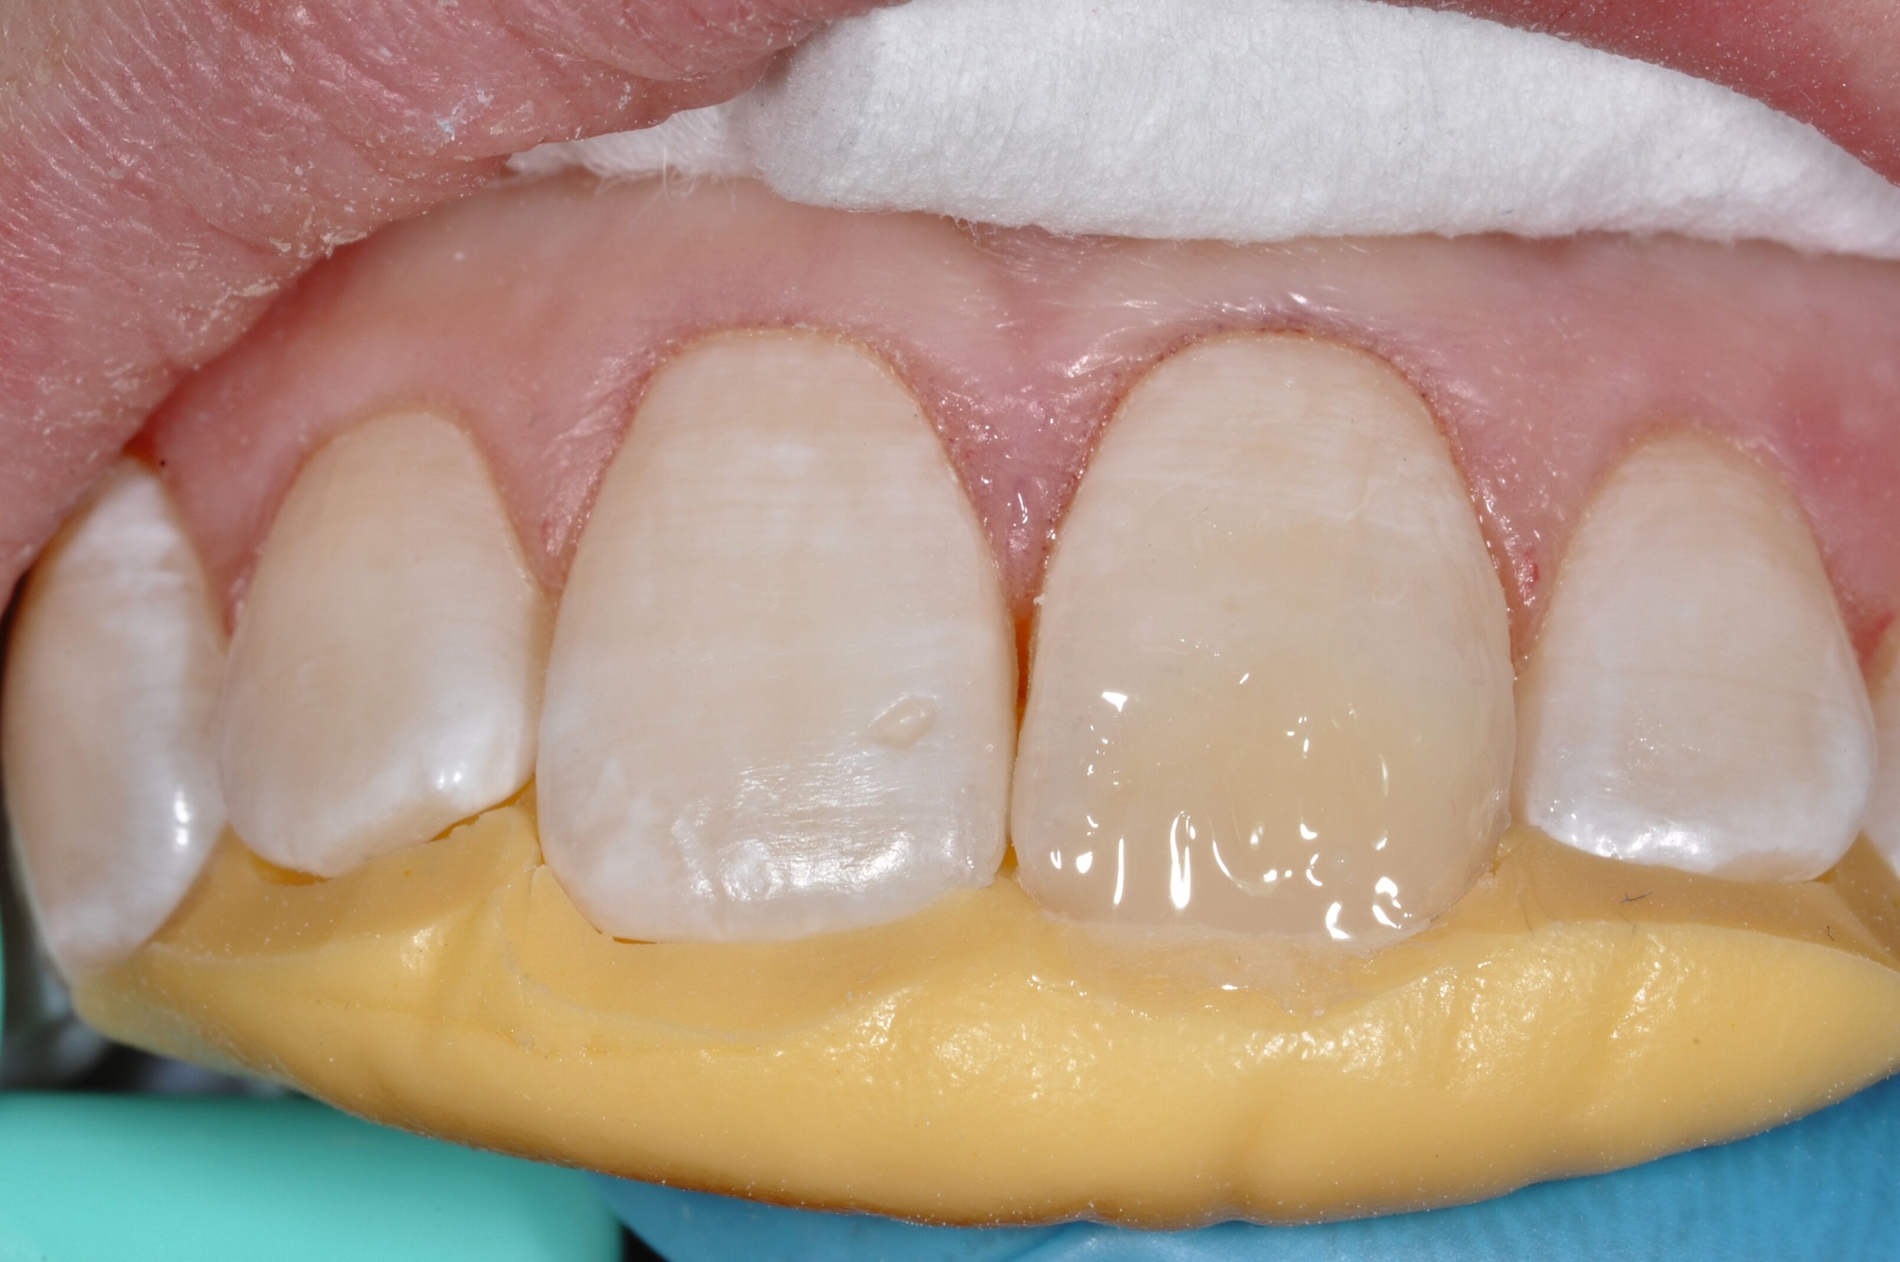

Diese Klassifikation dient als Grundlage für die Therapieempfehlungen. Deutlich wird, dass aufgrund der Symptomatik die Therapie der Zähne höchst unterschiedlich ausfällt. Dass etwa eine Opazität ohne Überempfindlichkeit (Index 1, Abbildung 1) ein anderes therapeutisches Vorgehen erfordert als ein Zahn mit nahezu komplettem Einbruch der Zahnoberfläche und mit Hypersensitivität (Index 4, Abbildung 2), ist offensichtlich.

Für die zahnärztliche Praxis gibt die Einteilung eine Orientierung darüber, welche Behandlungsmaßnahmen erforderlich sind beziehungsweise eingesetzt werden können. Je nach Schweregrad wird dabei zwischen nichtinvasiven und invasiven Maßnahmen sowie einer kurzzeitigen oder längerfristigen, restaurativen Therapie unterschieden. Bei der Überarbeitung des Konzepts wurde zudem zwischen Front- und Seitenzähnen differenziert (Abbildung 3) [Bekes et al., 2023; Steffen et al., 2017].

Die Versorgung der MIH-Frontzähne entspricht dem Vorgehen im Seitenzahnbereich. Problematisch ist die Maskierung der Opazitäten. Dazu müssen opake Komposite verwendet werden und es muss eine Schichtstärke von circa 1,5 mm garantiert sein (Abbildung 9).